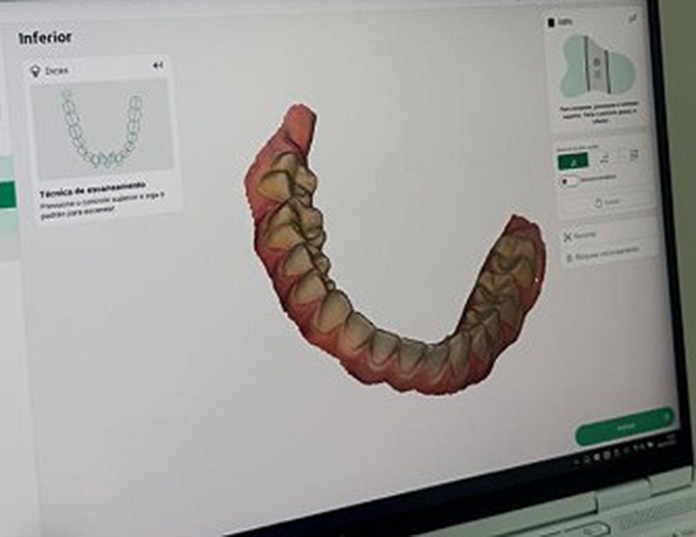

As Facetas de Porcelana mimetizam o esmalte dos dentes. Elas têm a durabilidade do esmalte dental. Elas podem desgastar, quebrar e soltar caso os dentes não estejam bem engrenados na mordida. Por isso é importante um planejamento bem feito e a manutenção periódica da reabilitação.

Depende da necessidade estética. Dente escurecido ou mal posicionado sofre maior desgaste. Dente com a cor natural e bem posicionado sofre menor desgaste.